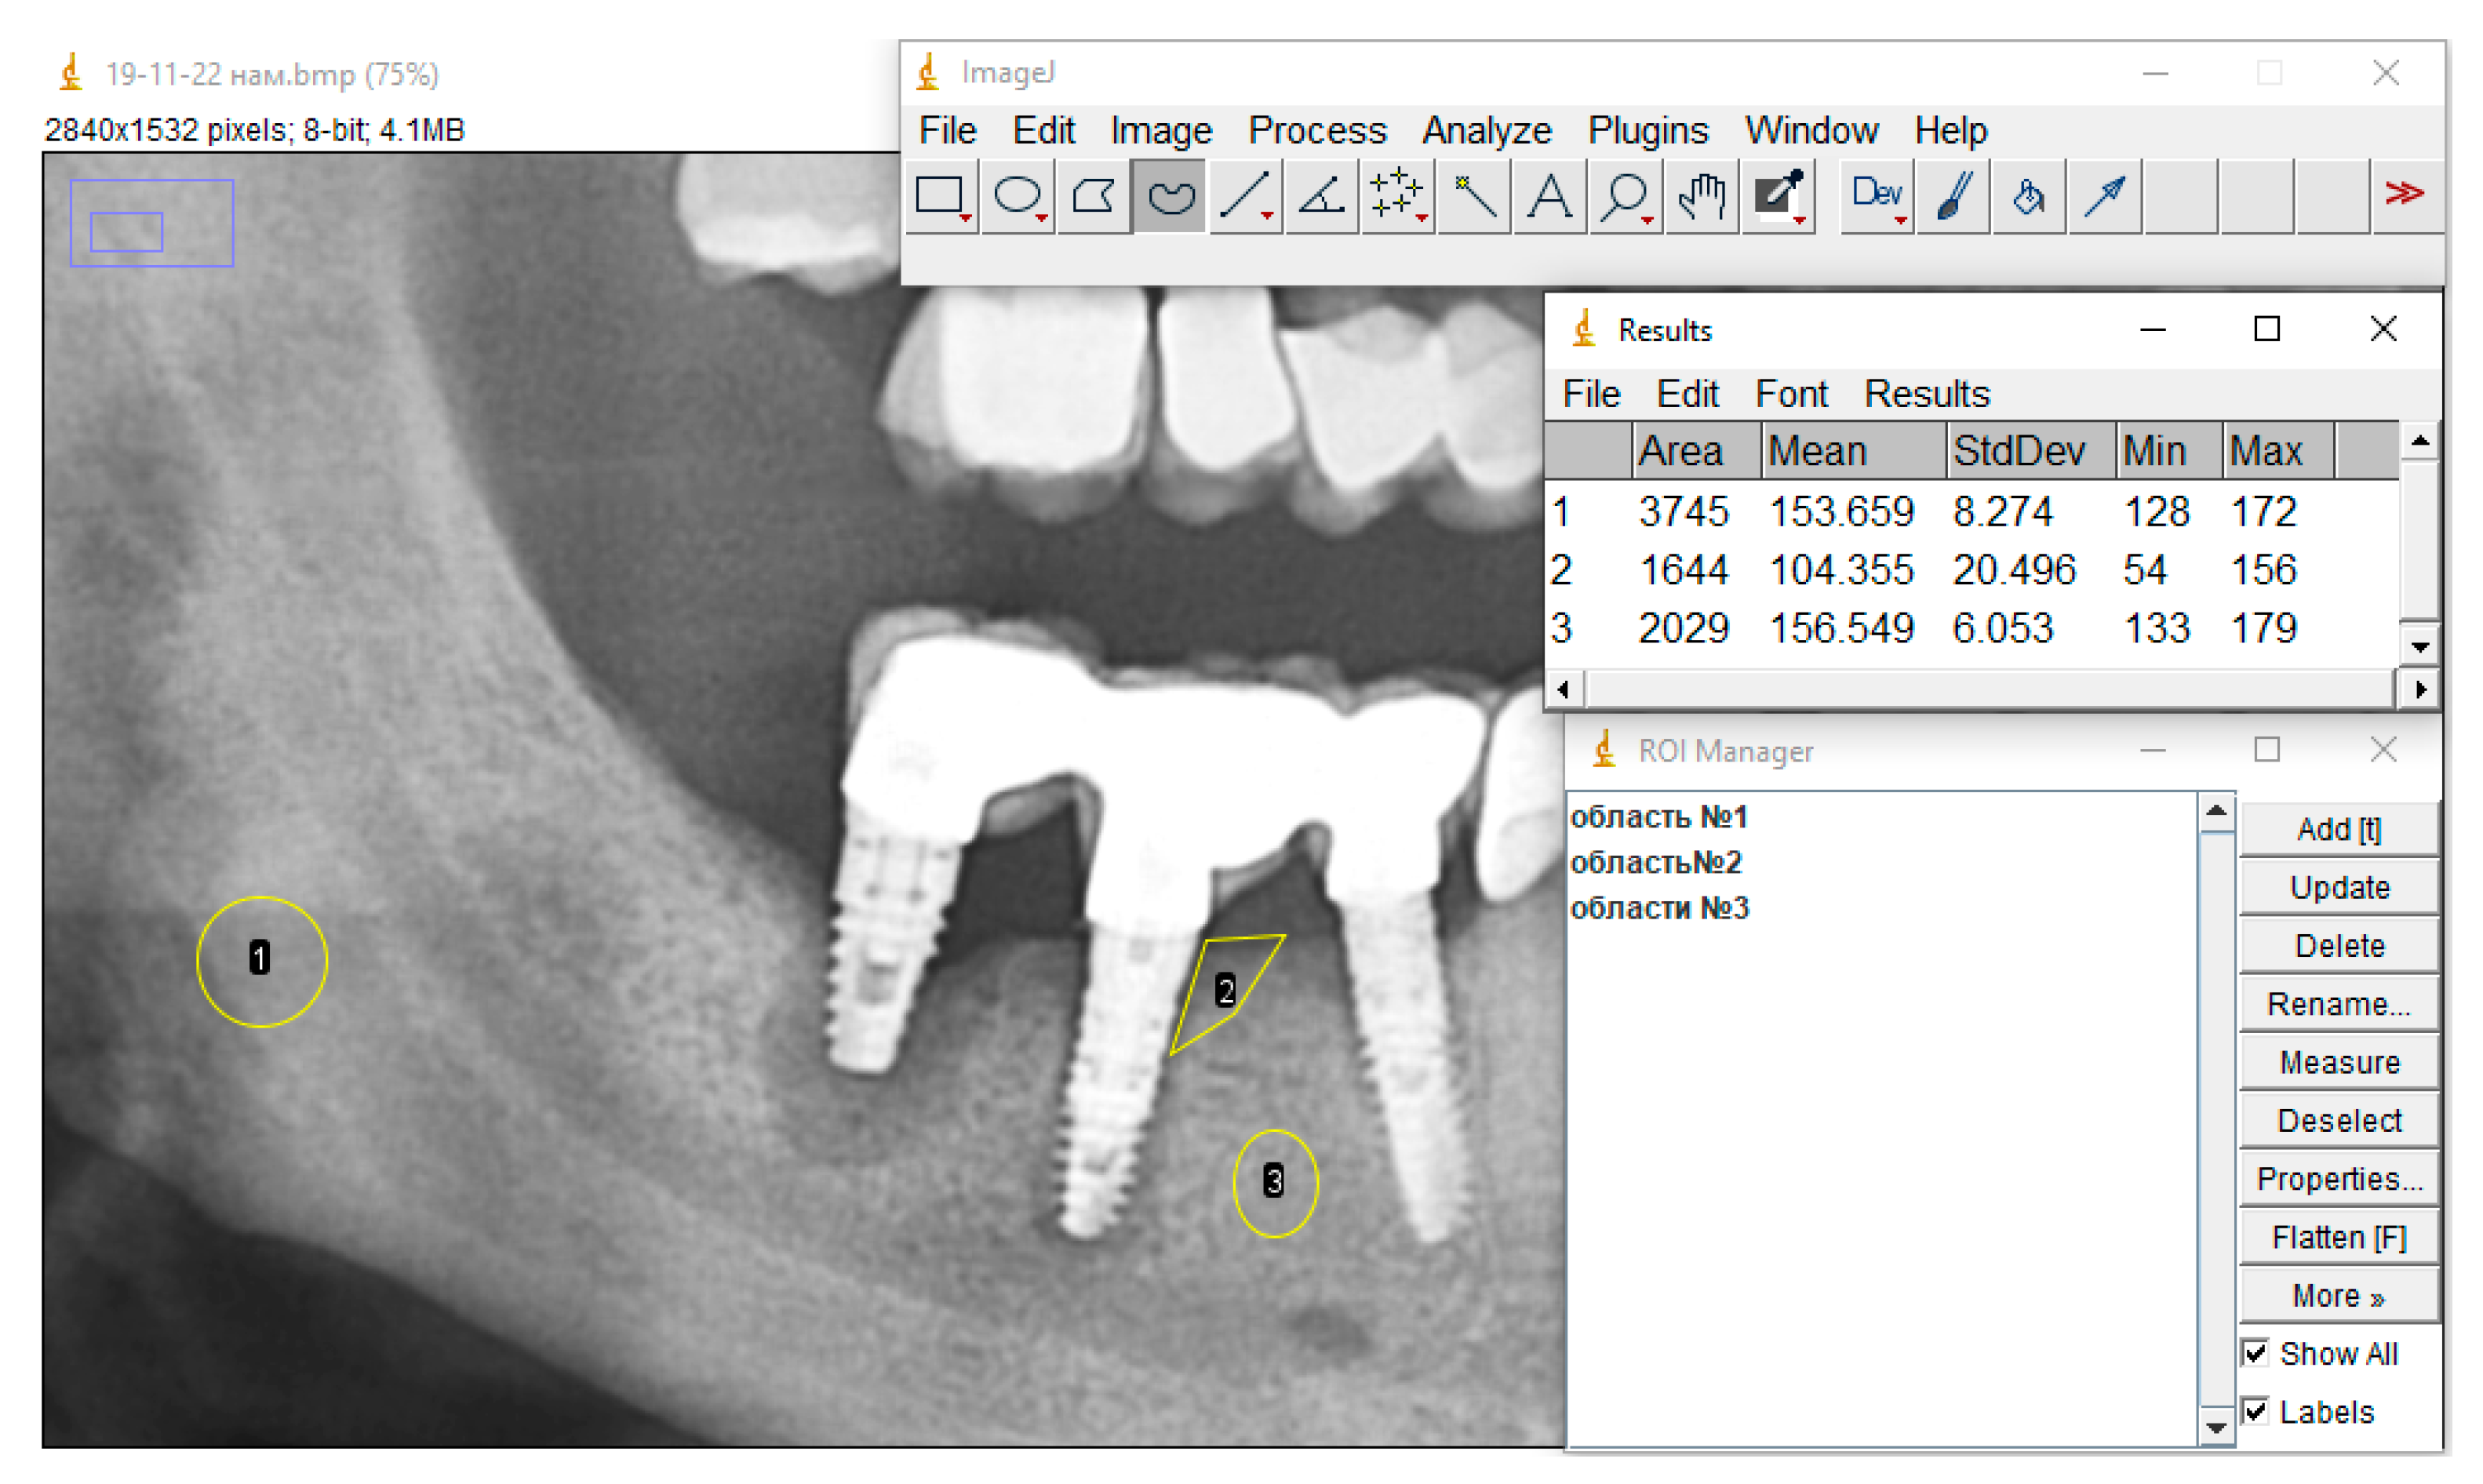

- Take the necessary measurements. If there is only one selection area, then the Analyze > Measure command for the previously set Set Measurements parameters in the special “Results” window will display the measurement results. If ROI Manager was used and many ROIs were selected, then to get the result one must select the Measure item (Figure 3).